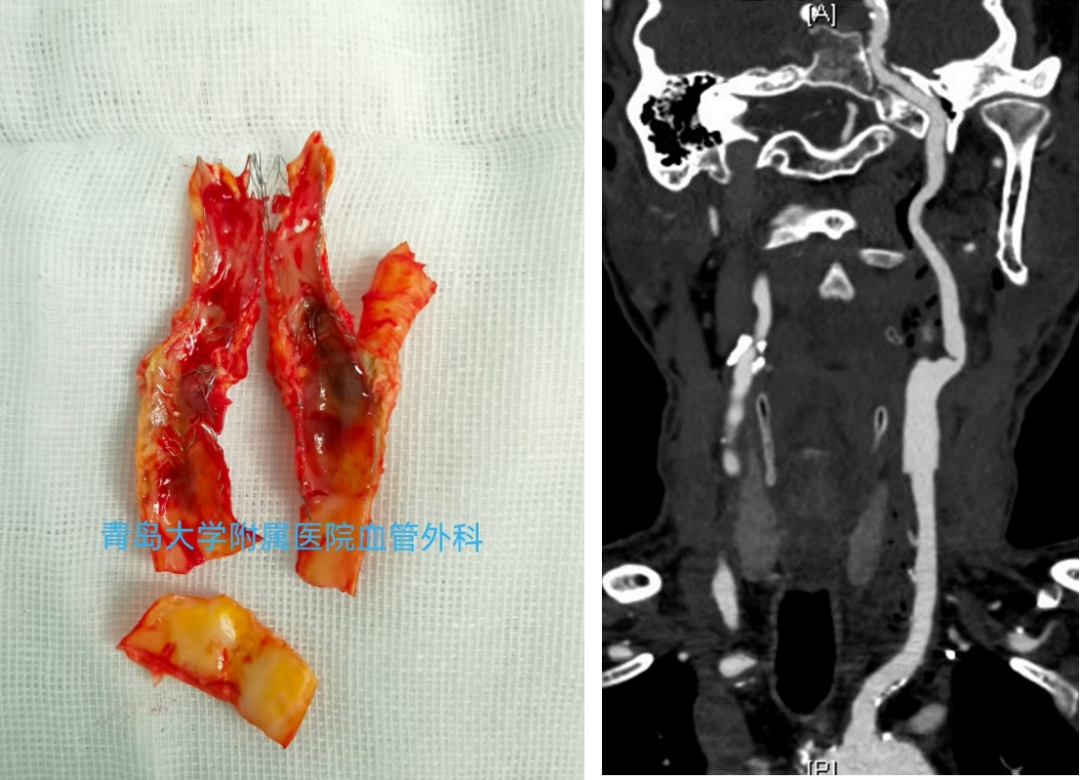

CASE 1:79岁男性,双侧颈动脉重度钙化狭窄,采用IVL预处理后置入支架,术后造影显示管腔通畅。

双侧颈动脉重度

钙化狭窄

IVL后管腔

获得良好

术后造影

显示管腔通畅